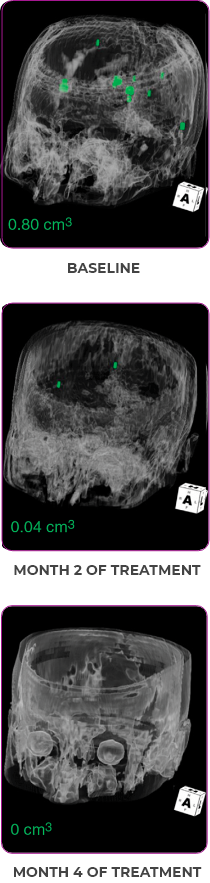

Response in primary and metastatic lesions1

MRIa imagery of the brain. Green circles indicate baseline brain metastases.1

SCAN 2: BRAIN

aMRI, magnetic resonance imaging.

MRIa imagery of the brain. Green voxels indicate decreased burden of metastatic disease; further quantified by accompanying measurement in green.1

SCAN 3: BRAIN

Pre- and post-treatment imaging, by Rosen EY et al, is licensed under Creative Commons License CC BY 4.0.

Response to VITRAKVI1,2

- Partial response to treatment that was confirmed at 2 months (34% tumor reduction)

- Grade 1 cough and Grade 2 fatigue

- Patient remains on VITRAKVI after more than 4 months of treatment